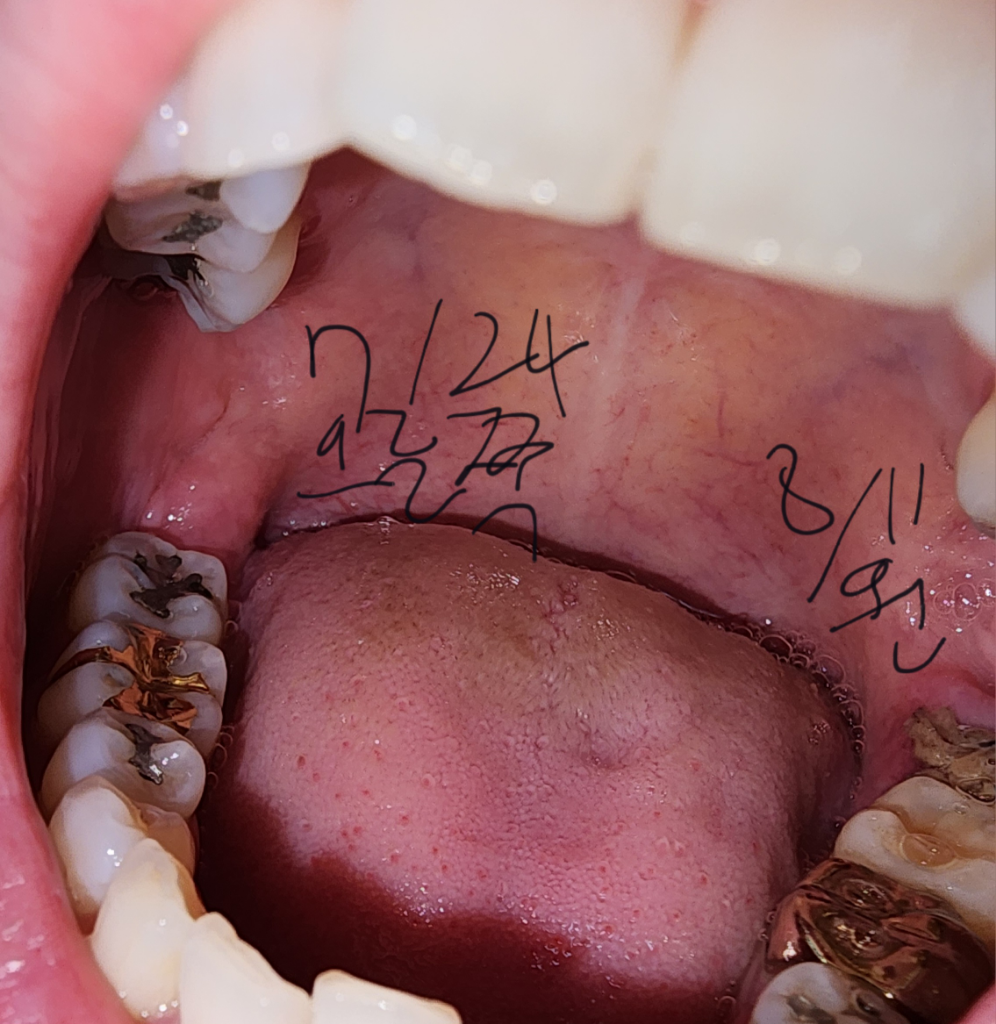

사진 첨부합니다 실밥을 엄청 꼬매주셔서 두쪽 다 드라이소켓같은건 전혀 발생한거같진않아요. 왼쪽 붓기도 아주천천히 빠지고있으나 어금니가아프고 찝힘등으로 잠들기어렵고 밥을못먹는데 어금니통증도 다 자연스러운걸까요? 제 치아상태를보면 그럴수있는건지 궁금합니다.

분명 해당 발치부위빼고 칫솔로 다 살살 닦고 혀클리너도쓰는데 저렇게 더러워요.....

• 2번 째 사진